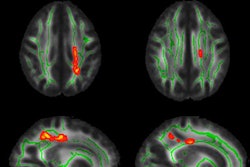

Based on the ADNI test, the deep-learning model achieved its highest marks in differentiating between patients with normal cognition and those with Alzheimer's disease. The model also performed well in separating patients with mild cognitive impairment from those with Alzheimer's. It fell short, however, in distinguishing between normal cognition and mild cognitive impairment.

"The tricky one clinically, obviously, is normal cognition versus mild cognitive impairment, which is a much more subtle difference, at only 0.69," Trivedi said.

As for the institutional UCSF dataset, the model was excellent in detecting Alzheimer's and normal cognition. However, it performed poorly in identifying mild cognitive impairment. Trivedi suggested the result could be due to the small sample size.